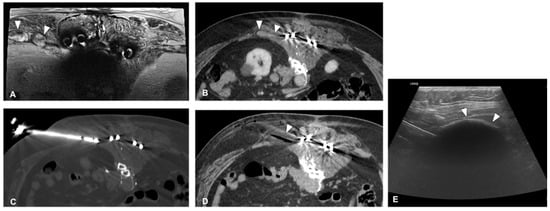

2.1. Recurrent Retroperitoneal Soft Tissue Tumors

- Fan, W.; Niu, L.; Wang, Y.; Zhang, Y.; Yao, X.; Tan, G.; Yang, J.; Li, J. Percutaneous computed tomography-guided cryoablation for recurrent retroperitoneal soft tissue sarcoma: A study of safety and efficacy. Oncotarget 2016, 7, 42639–42649. [Google Scholar] [CrossRef]

- Fan, W.-Z.; Niu, L.-Z.; Wang, Y.; Yao, X.-H.; Zhang, Y.-Q.; Tan, G.-S.; Yang, J.-Y.; Li, J.-P. Initial Experience: Alleviation of Pain with Percutaneous CT–Guided Cryoablation for Recurrent Retroperitoneal Soft-Tissue Sarcoma. J. Vasc. Interv. Radiol. 2016, 27, 1798–1805. [Google Scholar] [CrossRef] [PubMed]